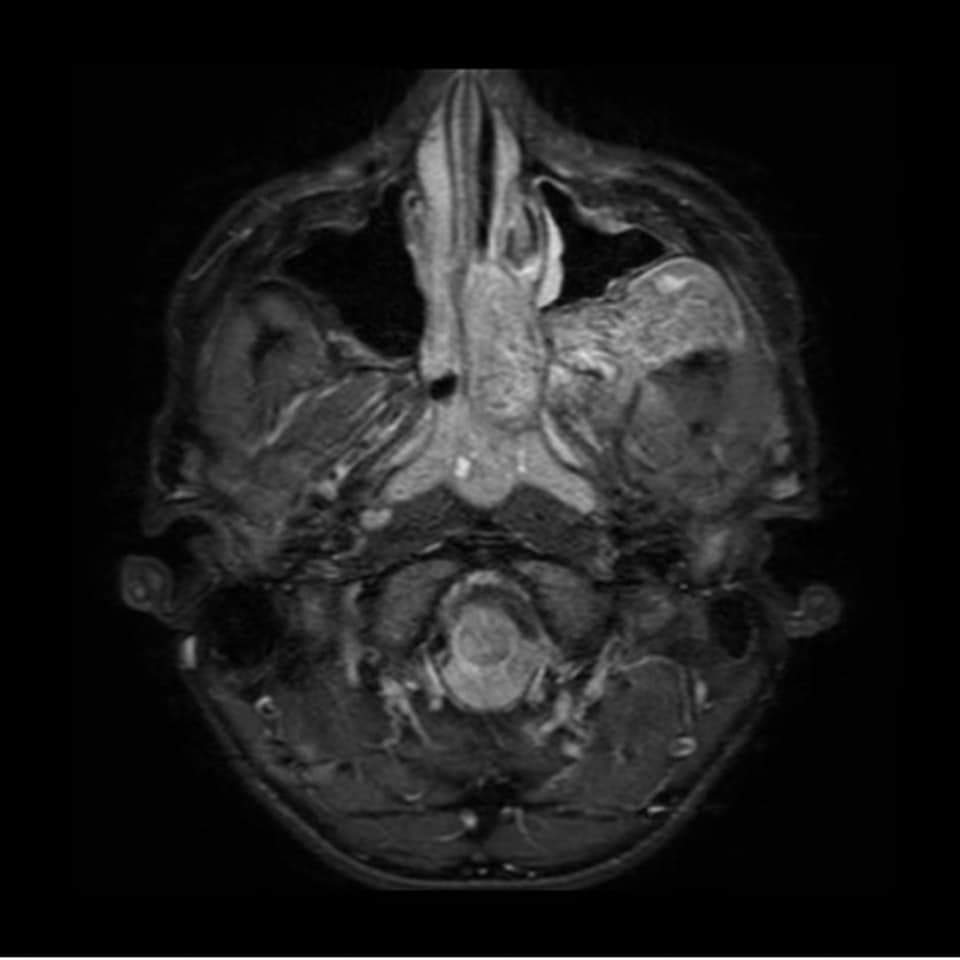

Angiofibroma Juvenil

Tumor benigno (no canceroso) formado por vasos sanguíneos y tejido fibroso. Los angiofibromas nasofaríngeos juveniles aparecen en la parte posterior de la nariz y a veces se diseminan a la parte superior de la garganta, los senos paranasales y los huesos que rodean...